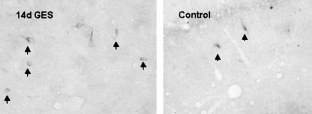

Compared with the control group, 2 h GES resulted in a decrease in the number of ghrelin-immunoreactive (ghrelin-IR) neurons in the hypothalamic paraventricular nucleus (PVN, 34.8 ± 1.86 vs 57.2 ± 2.95, P = 0.02) and the supraoptic nucleus (SON, 51.2 ± 3.21 vs 82.8 ± 3.08, P = 0.01); the CCK-immunoreactive (CCK-IR) neurons in the hippocampus were of no changes (7.4 ± 0.87 vs 6.2 ± 0.58, P = 0.29). After the 14-day GES, the number of CCK-IR neurons in the hippocampus was increased compared with that of the control group (4.0 ± 0.32 vs 2.4 ± 0.51, P = 0.03). However, there were no changes in the number of ghrelin-IR neurons either in the PVN or in the SON.

Fig. 2